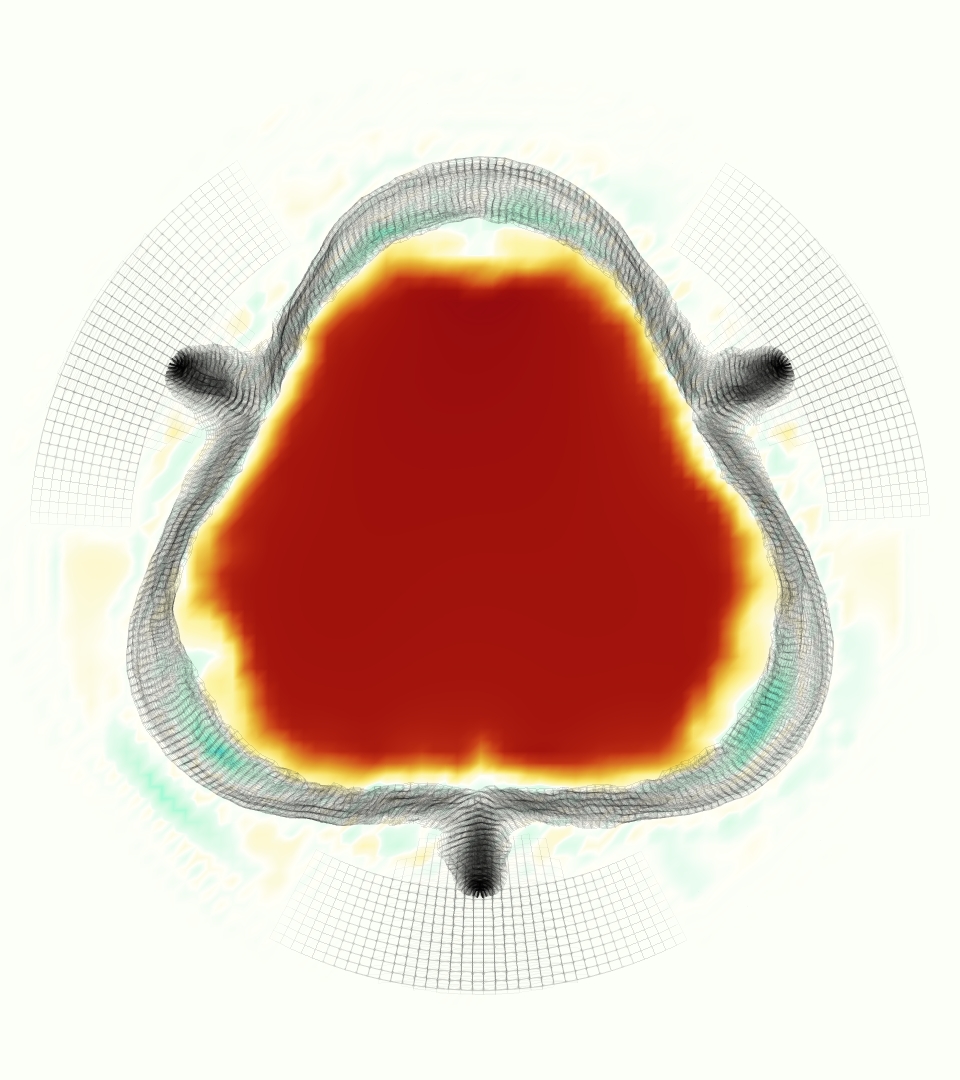

The gross morphology of the model valve that emerged from this process is shown in Figure 4. The free edge was 2.87 cm, corresponding to 3.3 cm in the predicted loaded configuration. After the pinching the leaflets together at the commissures, this left approximately 2.1 cm of free edge rest length per leaflet free to move independently of the other leaflets, within measurement error of ±0.1 cm from the free edge length of 2.2 cm measured on the prostheses. The leaflet rest height was 0.94 cm corresponding to a predicted loaded height of 1.44 cm. The measured leaflet height of 1.3 cm is nearly the predicted loaded height of 1.44 cm, which may be because the leaflets are so compliant in the radial direction, that pulling them flat to measure them achieved substantial stretches. The fiber orientation of the model runs from commissure to commissure and qualitatively matches experimental observations [38], though direct quantitative comparison is beyond the scope of this work. One minor limitation is that we do not add bending rigidity to the leaflets, beyond what emerges from the thickening process described above, and thus may not accurately capture leaflet flutter or other similar behaviors. Based on the thickness of mm, we estimated the mean tangent modulus at the predicted loaded stretches as dynes/cm2 circumferentially and dynes/cm2 radially. The prosthetic valve tissue is fixed in glutaraldehyde, and literature values for the fully-recruited circumferential tangent modulus of fixed porcine aortic valve tissue vary widely. Based on the experimental measurements of Billiar and Sacks and their constitutive law for valves fixed under 4 mmHg of pressure, we evaluated their constitutive law at the relevant stretches and and estimated the circumferential tangent modulus to be dynes/cm2 [6]. Rousseau et al. reported moduli ranging from to dynes/cm2, depending on the applied preload during fixation [36]. Sung et al. reported moduli ranging from to dynes/cm2, depending on fixation pressure [43]. Thus our estimated tangent modulus falls within the range of existing studies, so we considered our resultant modulus in good agreement given the complexity of the steps involved, phenomenological nature of the constitutive law and uncertainties in experiments. We do not have access to the precise material properties of the prosthetic valve, and further, the only literature we could find on the material properties of a similar prostheses reported the tangent modulus at one particular loading, which did not appear to be at a relevant stretch for comparisons with our model [19]. Thus, our model has material properties in a reasonable range for a fixed aortic valve prostheses (placed in the pulmonary position in our simulations), but it does not directly model the material properties of the prostheses.

We constructed the model vessel for FSI simulations from data from the MRI scans (Figure 4). The signal magnitude of 3D printed model material is distinct from the signal of the fluid in the scans, and we applied a thresholding operation to generate a three-dimensional model of the printed vessel surface. Using the MRI data ensured that the MRI and simulation coordinates were consistent in space and there were no alignment or registration errors. While using the files that generated the 3D printed model would have offered more spatial fidelity, the potential error in flow fields due to any mis-registration would have likely been much more substantial. Using Meshmixer (San Rafael, CA), we smoothed the mesh to remove stair-step effects and removed artifacts from the valve scaffold. We then remeshed to the desired edge length of 0.25 mm and extruded the model 0.25 mm and 0.5 mm to create a three-layer structure. As in the valve, this serves to eliminate the “grid aligned artifact” that can occur with pressure differences across thin membranes in the IB method [16]. Flow extenders of length 1 cm were added to the vessel at the inlet and both outlets to ensure that the normal to the vessel was aligned with the normal of the fluid box at the inlets and outlets. In FSI simulations, the vessel was held in place using target points, stiff springs of zero rest length that connect the current position of each model node to its desired position (Section 3.3). Additional linear springs are placed on each edge in the triangulated model. These springs are not meant to model a particular material and only serve to keep the vessel rigid and stationary throughout the simulation.

At = 0, the axial slice directly at the valve annulus shown in columns 1 and 2 in Figure 6, there was excellent agreement between the simulation and experiment over the cardiac cycle in the speed and shape of the jet through the valve. In both cases, the axial velocity increased as the flow accelerated during systole and the valve leaflets opened, then decreased during diastole with slight negative velocity before the valve leaflets were fully closed. The forward flow through the valve annulus did not form a full circle, but rather developed a triangular shape with a point of the triangle forming along the interior curve of the vessel, at the bottom of the axial slices. At = 0, the points of this triangular jet shape aligned with the commissures of the valve. This shape persisted during peak systole and was well-matched by the simulation.

The axial slice = 0.625 cm, shown in columns 3 and 4 in Figure 6, cut through the support scaffolding of the valve and the leaflets when they are open. In the experimental data, the shape of the jet changed as it moved downstream. A triangular shape occurred, but the points were then aligned with the middle of each open leaflet as opposed to the commissures. Those points were also more rounded than they were at = 0. The peak velocity of the jet was faster at = 0.625 cm than at = 0, as the flow accelerated through the open valve leaflets. The simulation produced these features at = 0.625 cm. The triangular shape of the jet shifted similarly, and its speed increased compared to the upstream slice. As the flow decelerated into diastole, the jet shape remained roughly triangular but diminished in intensity before disappearing after valve closure.

The jet continued to develop at = 1.25 cm, an axial slice immediately downstream of the valve scaffolding and open leaflets, shown in columns 5 and 6 in Figure 6. In the experimental data, the points of the triangular jet shape extended further towards the vessel wall. In addition, regions of reversed flow developed in the locations downstream of the commissures, resulting in curved sides to the shape of the jet. Each tip of the jet was unique, due to variations in the individual leaflets in the physical bioprosthetic valve. These variations are apparent in the velocity fields, possibly because the jet edges are similar enough cycle to cycle that irregularities are still being captured even with phase averaging. Further discussion of these features can be found in Schiavone et al. [39], which showed that the jet tip shapes occurred in different pulmonary anatomies, demonstrating that they were likely due to inherent properties of each leaflet. The leaflets in the mathematical model of the valve are identical, so these nuances in leaflet variation could not be replicated. The simulation did capture some of the extension of the tips of the jet, as they were closer to vessel wall at slice = 1.25 cm than = 0.625 cm. The curves in the triangular sides of the jet were also present in the simulation, though they were less pronounced than the experimental data. At both = 0.625 cm and = 1.25 cm, the jet shape in the simulation was smoother than the jet in experiment. It is possible that the free edges of the leaflets in the mathematical model are not fully replicating the behavior of the physical leaflets of the bioprosthetic valve, in particular the amplitude or frequency of leaflet flutter, leading to the variations seen in the jet shape at = 1.25 cm downstream of the leaflet edges. The simulation, however, does capture the key features of the triangular shape and speed of the jet. Overall, qualitative comparisons demonstrated that the simulation reproduced key features of the flow during systole and diastole.